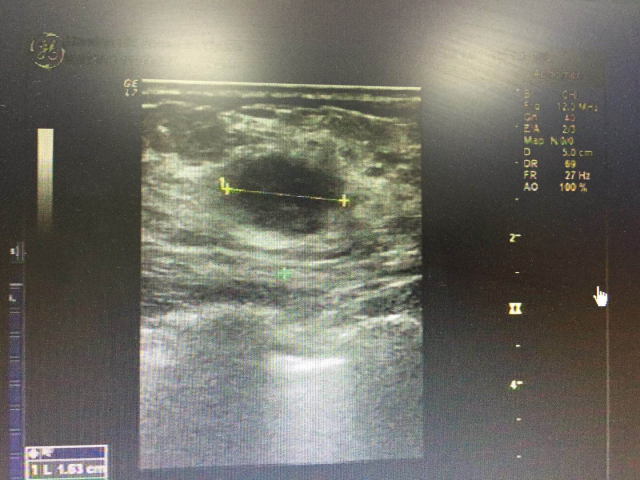

乳腺彩超显示:

1. 双侧乳腺增生;

2. 左侧乳腺低回声结节;

3. 左侧腋下低回声结节,考虑:肿大淋巴结,请结合临床及其他检查。